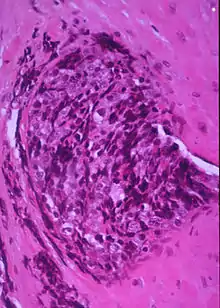

Small blue round cells of Ewing Sarcoma

In histopathology, a small-blue-round-cell tumour (abbreviated SBRCT), also known as a small-round-blue-cell tumor (SRBCT) or a small-round-cell tumour (SRCT), is any one of a group of malignant neoplasms that have a characteristic appearance under the microscope, i.e. consisting of small round cells that stain blue on routine H&E stained sections.

These tumors are seen more often in children than in adults. They typically represent undifferentiated cells. The predominance of blue staining is because the cells consist predominantly of nucleus, thus they have scant cytoplasm.[1][2]